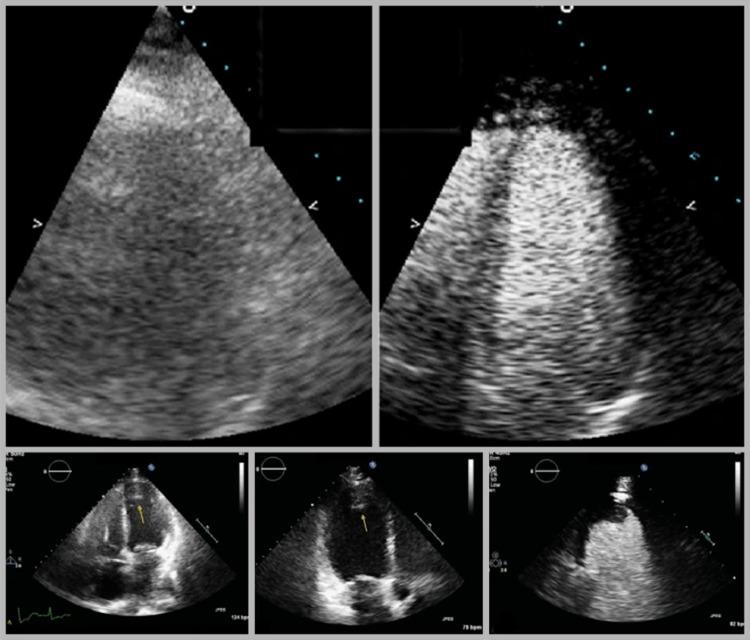

Contrast Echocardiography in VV-ECMO-Dependent Patients with COVID-19.新冠病毒病依赖静脉-静脉体外膜肺氧合患者的对比超声心动图

J Am Soc Echocardiogr. 2020 Nov;33(11):1419-1420. doi: 10.1016/j.echo.2020.07.012. Epub 2020 Jul 17.